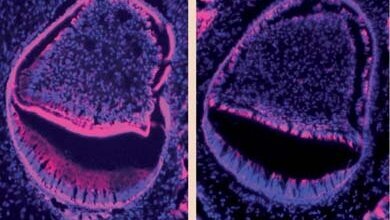

Kwasy tłuszczowe Omega-3 mogą zwalczać bakterie w jamie ustnej

Wyniki nowych badań dają podstawy do przypuszczeń, że korzystne działanie kwasów tłuszczowych Omega-3 może również dotyczyć sfery ...